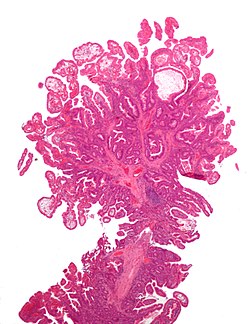

7

Diagnosis?

Inflammatory polyp -- very low mag.jpg

Adenocarcinoma

Colorectal mucosa within normal limits

Ganglioneuroma

Hyperplastic polyp

Inflammatory polyp

Juvenile polyp

Peutz-Jeghers polyp

Sessile serrated adenoma

Traditional serrated adenoma

Tubular adenoma

Tubulovillous adenoma

Villous adenoma

Xanthomatous polyp